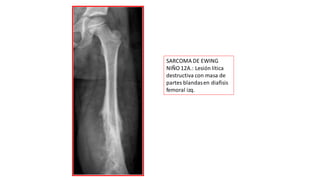

SARCOMA DE EWING

NIÑO 12A.: Lesión lítica

destructiva con masa de

partes blandasen diafisis

femoral izq.